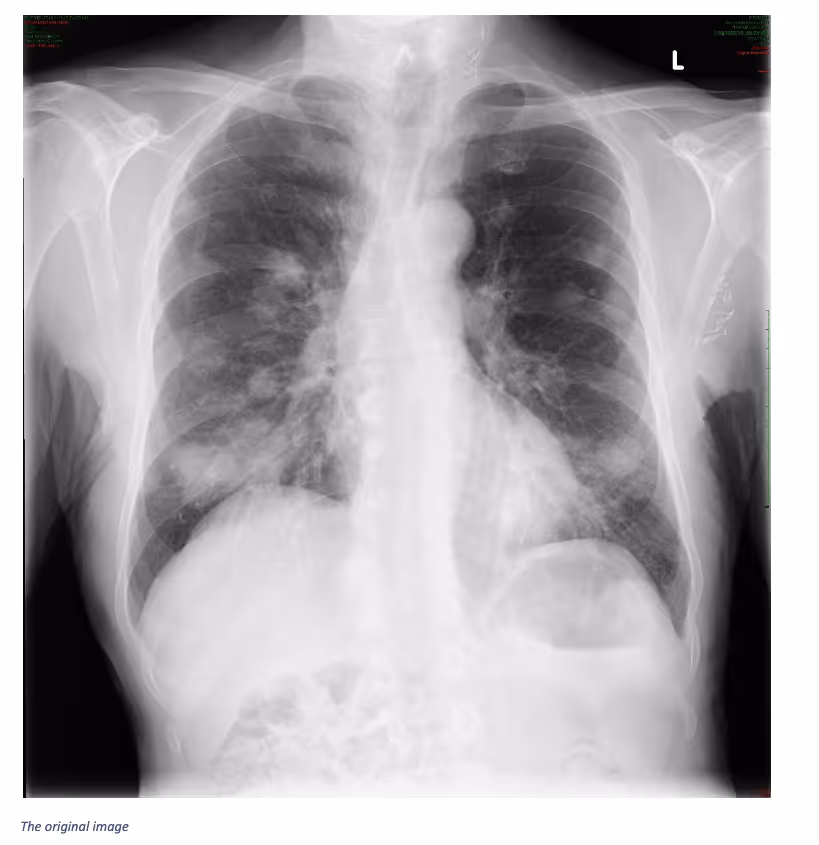

VinBrain Case Study: Detection of Multiple Lung Nodules on Chest X-ray

Ferrum Health partners with best-in-class AI providers offering solutions designed to reduce radiology workload and improve patient care.VinBrain Case Study: Detection of Multiple Lung Nodules on Chest X-rayIntroductionDetecting lung nodules on a chest X-ray image is an important first step in assessing a patient. These images can help the physician identify the size, shape, and location of lung nodules, as well as other characteristics, like calcium deposits. From there, they may recommend additional tests to rule out cancer or to determine other underlying issues.Clinical case

- A 55-year-old female patient came to the hospital complaining of night sweats and dyspnea

- Her medical history included a previous head and neck malignancy

- A chest x-ray was ordered

- Image findings

- Multiple lung nodules and masses in both lungs of variable size

- No internal cavitation

- Normal mediastinal contours

- Heart size normal

- Surgical clips in the left axilla